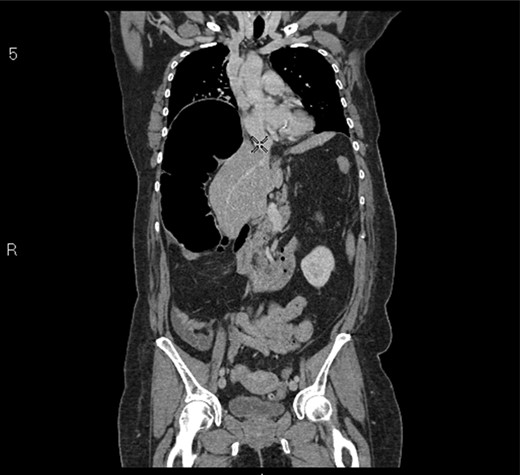

A 58-year-old female with a past medical history of a large intrathoracic hiatus hernia presented to her general practitioner and was subsequently referred to our surgical department with symptoms of sudden onset severe epigastric pain associated with vomiting and abdominal distension. Her abdomen was generally tender, maximally in the epigastric region, although she was not peritonitic. The admission erect chest radiograph showed a large hiatus hernia and an elevated right hemidiaphragm with a large loop of distended bowel (Fig. 1). Subsequent computed tomography (CT) scan demonstrated an almost completely intrathoracic stomach with a degree of volvulus, and the liver medially displaced by a loop of large bowel felt to be caecum (Fig. 2). Since the patient remained otherwise well, bidirectional endoscopy was performed, and given that a volvulus point could not be identified and the ileocaecal junction was not identified, contrast studies were requested (Figs 3–5) which demonstrated an incomplete obstruction caused by a volved caecum rotated anteriorly and cephalad.

CT coronal section demonstrating caecum medially displacing the liver and causing an upward pressure on the right hemidiaphragm.

Radiological imaging is useful in diagnosing caecal volvulus. Rosenblat et al. [8] found that CT findings of whirl, ileocaecal twist, transition points, X marks the spot and split wall have high specificity for caecal volvulus. Additionally, they found that the absence of distal colonic decompression made the diagnosis of caecal volvulus unlikely. Diagnostic confusion may exist between sigmoid and caecal volvulus; however, the location of the mesenteric twist (CT whirl sign) is highly accurate in distinguishing the two [9]. This whirl sign, as first published by Fisher [10], describes ‘swirling strands of soft tissue attenuation within a background of fat attenuation and gives the appearance of a hurricane on a map’. Barium enema has been historically used to confirm the presence of a volvulus, assess the distal colon and may also have a therapeutic effect [3].